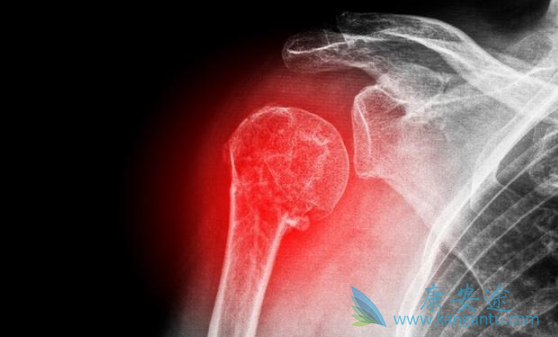

尤文氏肉瘤和骨肉瘤是儿童和青年人最常见的骨原发恶性肿瘤。具有恶性程度高、易转移、预后差等特点。受限于治疗手段,骨肉瘤标准治疗以大剂量的化疗以及手术治疗广泛的切除肿瘤为主,而尤文氏肉瘤主要以放疗联合化疗为主,暂时无靶向药可用。2018年ESMO会议上公布的最新研究显示:多靶点抑制剂卡博替尼(Cometriq)对尤文氏肉瘤和骨肉瘤具有很强的抗肿瘤活性,为这两种骨原发恶性肿瘤提供了治疗新选择。